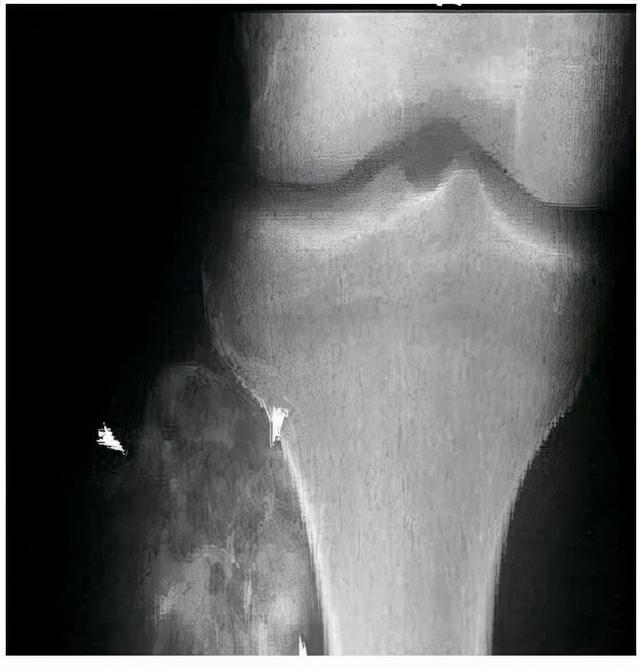

3.骨肿瘤的疼痛集中在固定点,如膝关节,容易红肿,而生长痛则没有。总之,如果孩子在家喊腿疼,家长一定不要大意,观察孩子的具体症状,以免在不知情的情况下耽误机会。如果实在不放心,最好去医院检查一下,由医生诊断。